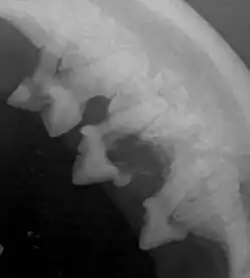

Das Zahnfleisch ist stark gerötet, ödematisiert und eventuell treten Zubildungen (Hyperplasie) des Zahnfleisches auf. Die eigentlichen Läsionen am Zahnhals sind daher meist nicht sichtbar. Die Diagnose kann anhand einer Sondierung der Zahnfleischfurche und der Anfertigung einer Röntgenaufnahme gestellt werden. Letztere zeigt einen Knochenabbau in Zahn und Zahnwurzel.

Bei dieser Form erscheinen klinisch daher die Zähne zunächst gesund und allenfalls kleine, örtlich begrenzte Zahnfleischentzündungen sind sichtbar. Erst mit der weiteren Aushöhlung des Zahns und eventuellen Ausbrüchen der Zahnkrone werden die Prozesse sichtbar. Bei der Röntgenuntersuchung ist der Knochenabbau in Zahn und Zahnwurzel sichtbar. Die Zahnfleischfurche lässt sich nicht sondieren.

Die Diagnose kann anhand des klinischen Bildes, der Sondierung und einer Röntgenuntersuchung gestellt werden. Bei der Sondierung mit einer scharfen Sonde zeigen Katzen das typische, auf Zahnschmerzen hinweisende Zähneklappern („Chattering“). Es ist zu beachten, dass zum röntgenologischen Nachweis ein Dichteunterschied zwischen normalen Zahngewebe und Läsion von 40 % notwendig ist, Frühstadien also übersehen werden können.[2]